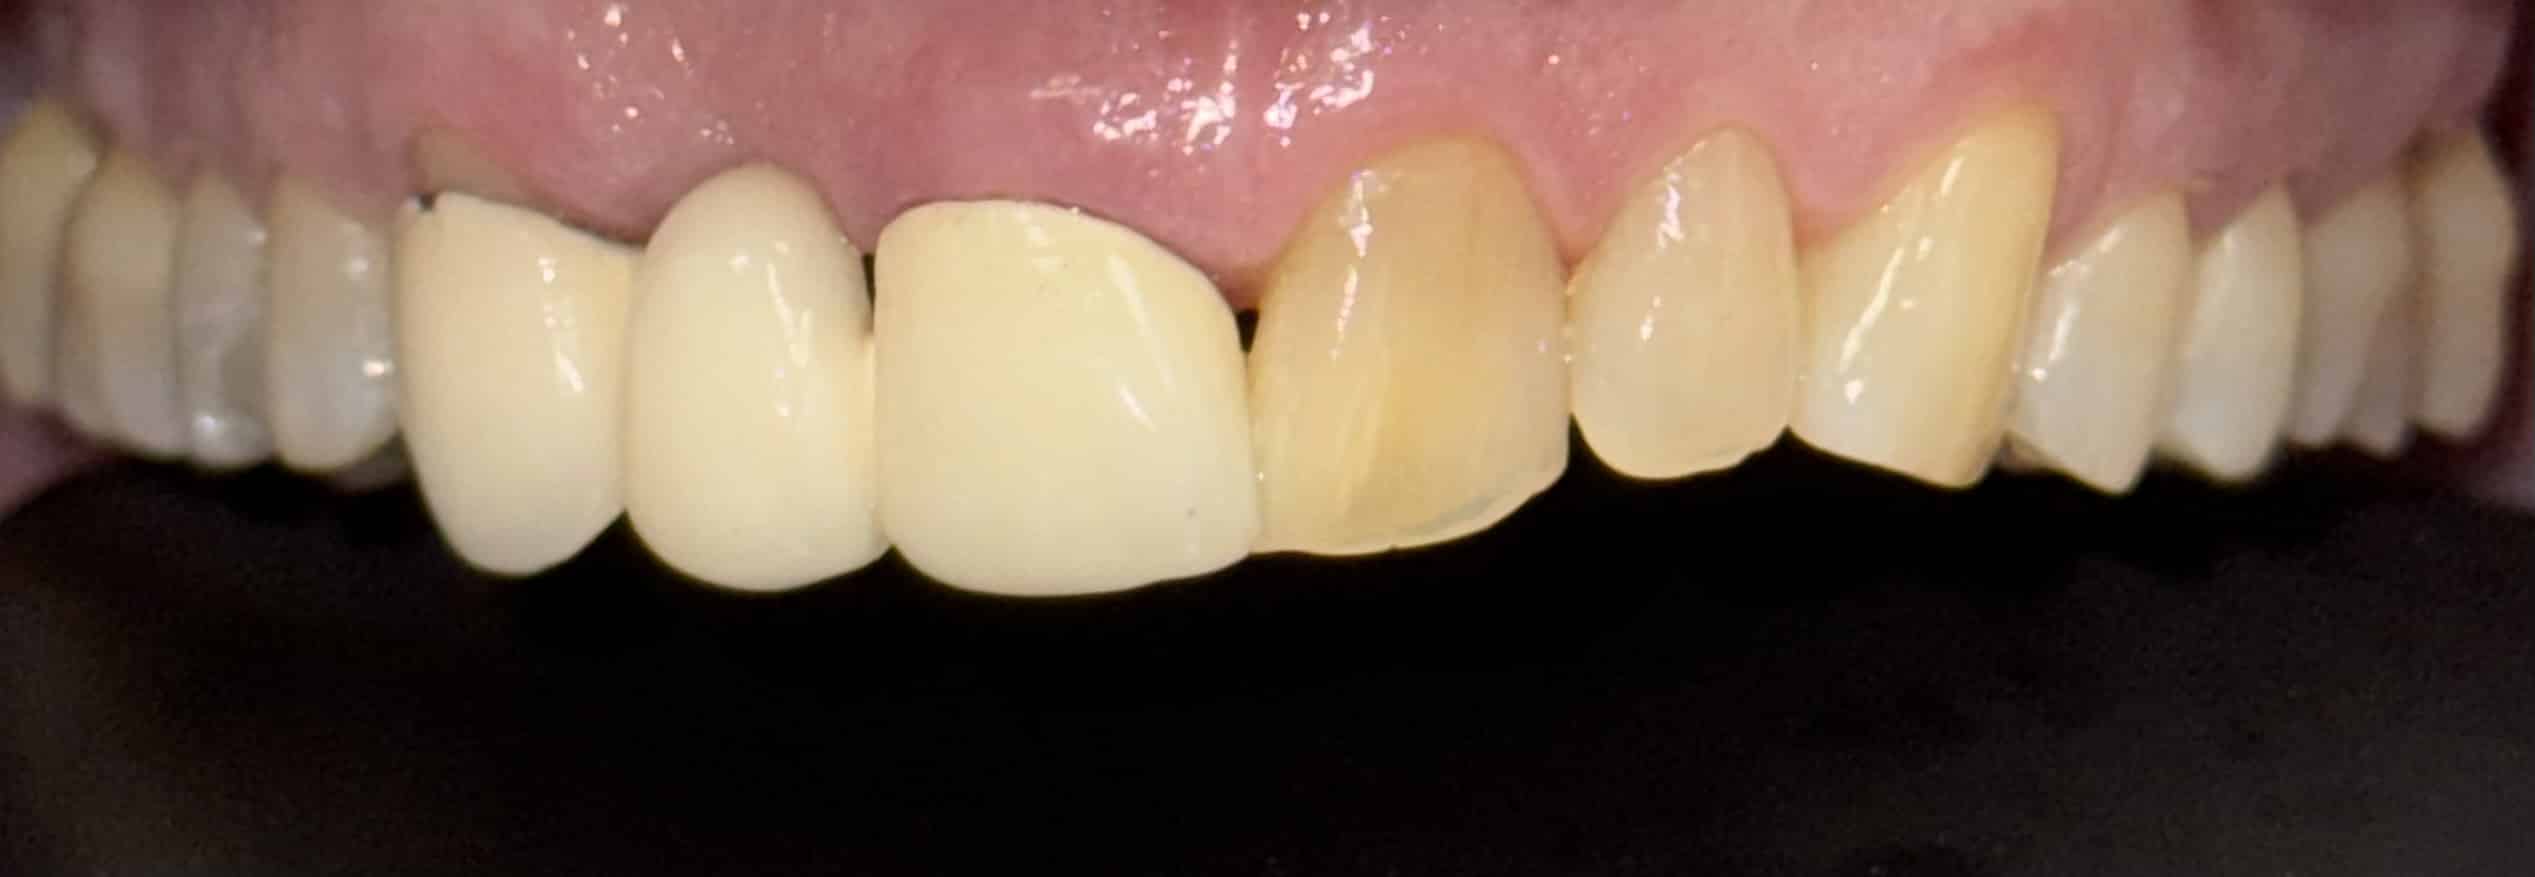

Before and After Image Gallery